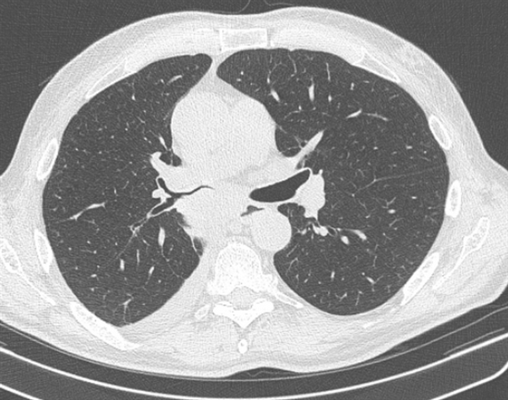

Фото 1 — Центральный рак правого нижнедолевого бронха (1) с обтурацией и метастазами (2) в бифуркационные лимфатические узлы

Фото 2 — Периферический рак (1) верхней доли правого легкого

КТ-признаки центрального рака легкого: при компьютерной томографии определяется объемное образование мягкотканной структуры, в котором «обрывается» просвет нижнедолевого бронха. Края образования бугристые, неровные, со спикулами, форма неправильная.

Центральный рак легкого на КТ. Обратите внимание на различия в ширине просвета центральных бронхов справа и слева. Просвет правого верхнедолевого бронха не виден. Виден ателектаз верхней доли. В круге - непосредственно само опухолевое образование, ставшее причиной ателектаза.

Типичный периферический рак легкого (аденокарцинома) на МСКТ. Справа в 6 сегменте легкого выявлен плотный мягкотканный узел со спикулами, деформирующий и подтягивающий к себе междолевую плевру.